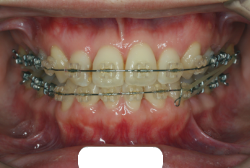

「歯並びの凸凹を直したい」という主訴で来院したケースです。診断の結果、たしかに「叢生」という隙間が足りないと言うことが原因の凸凹症例でした。

しかし、それ以上に問題なのは「前歯の噛み合い方が深すぎる」という症状で、初診の歯の正面写真を見ると下の前歯が全く見えません。こういう症状を矯正学では「過蓋咬合(かがいこうごう)」と言います。過蓋咬合を放置すると、将来的に顎関節に悪影響を与えるとされており、顎関節症の原因因子の一つです。また下の前歯の先端が、上の前歯の裏側の歯茎と強く接触するため、歯周病の原因にもなります。

検査の結果、凸凹が軽症なため非抜歯で矯正すること可能と判断、マルチブラケット装置にて治療しました。治療後は歯並びが綺麗になっただけでなく、噛み合わせ的にも正しい状態が確立しています。